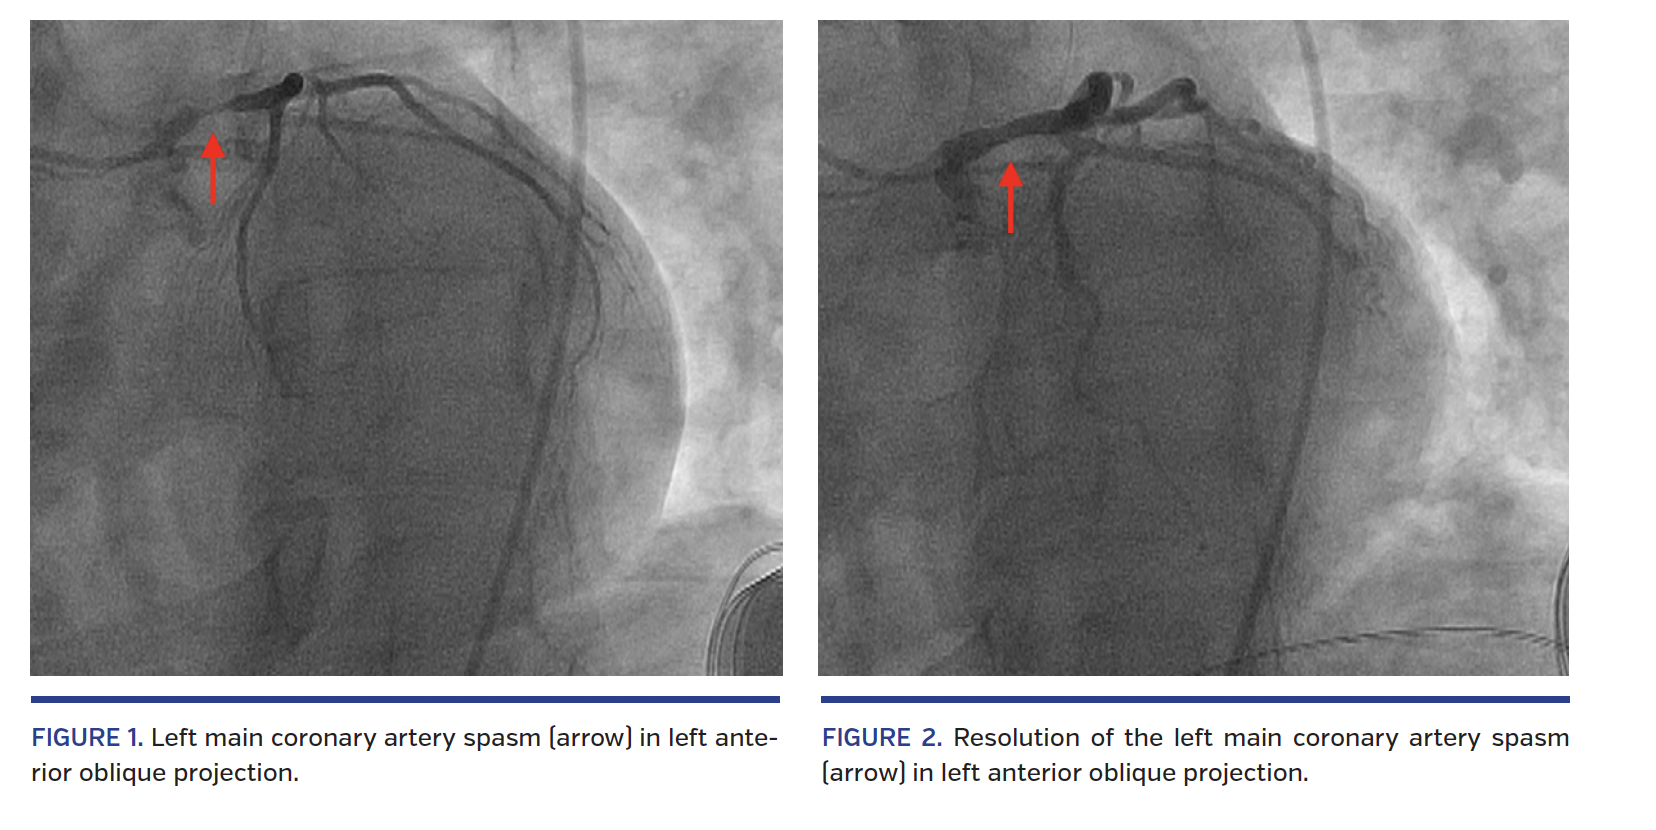

Persistent Catheterinduced Coronary Artery Spasm ppt download

Persistent Catheterinduced Coronary Artery Spasm ppt download Spasm With Catheter And, people with a neurological disorder, such as ms or a spinal cord injury, may experience. Bladder spasms may occur because the catheter is unstable inside the bladder, as a result of a neurogenic bladder, an irritable. Medical conditions such as neurogenic bladder, multiple sclerosis,. Bladder spasms can also be symptoms of neurogenic bladder. Bladder spasms can be painful and. Spasm With Catheter.

CatheterInduced Coronary Spasm Serious But Preventable Spasm With Catheter Bladder spasms can be painful and often lead to an urge to urinate. Inserting a catheter can irritate your bladder, causing spontaneous, painful spasms. Bladder spasms happen when your bladder muscles tighten or contract. Incontinence may occur if the bladder spasms continue because the. Ureteral stents (tubes to help drain the kidney and. Urinary tract infections and irritation from using. Spasm With Catheter.

Catheterinduced Coronary Spasm A Beginner's Trap Journal of the Spasm With Catheter Urinary tract infections and irritation from using a catheter are also common culprits. Ureteral stents (tubes to help drain the kidney and. Bladder spasms can also be symptoms of neurogenic bladder. Medical conditions such as neurogenic bladder, multiple sclerosis,. Bladder spasms happen when your bladder muscles tighten or contract. Incontinence may occur if the bladder spasms continue because the. These. Spasm With Catheter.